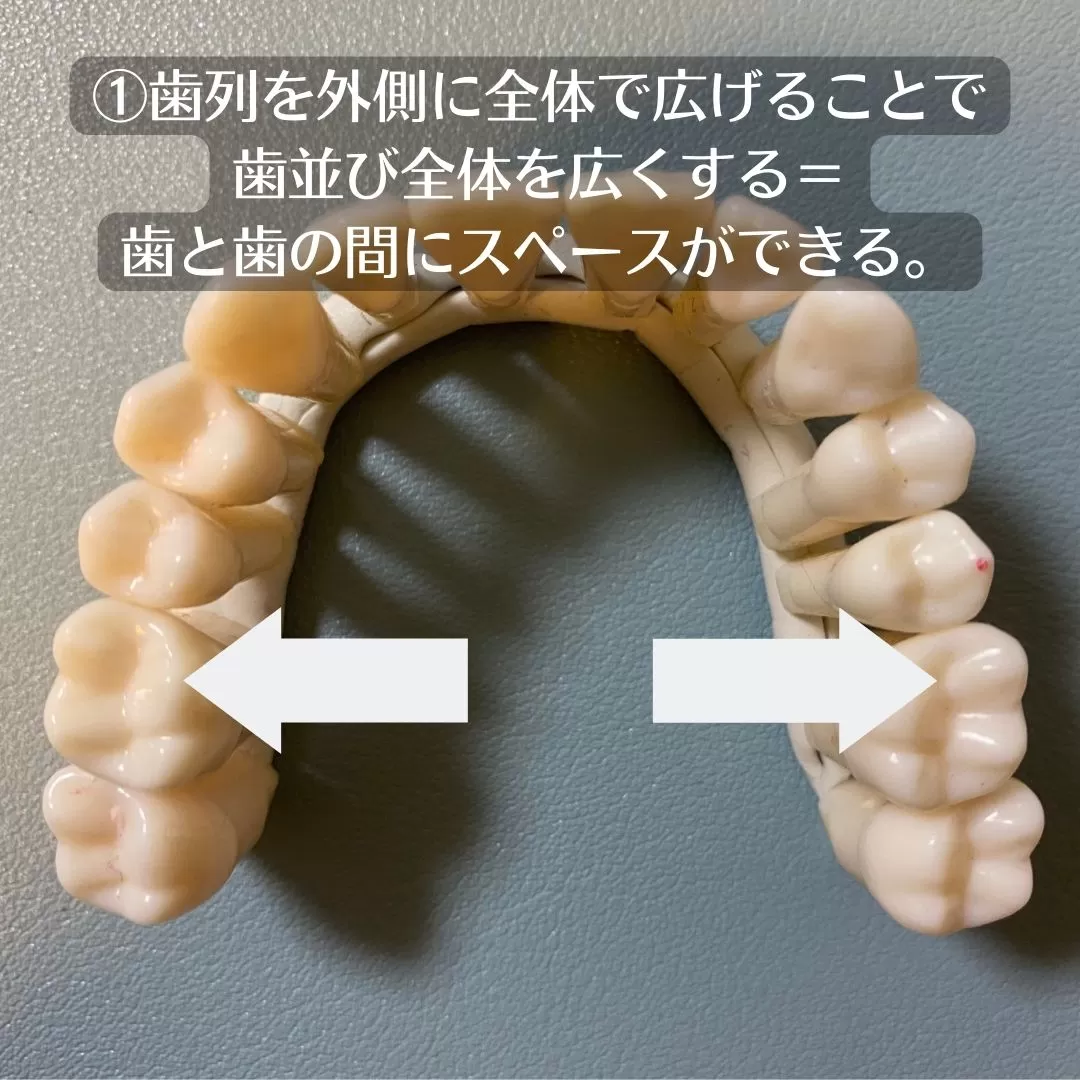

今回のケースはスペースを求めて

【拡大】ということをしています。

歯の軸を起こしましてスペースを作るのです。

奥歯の噛み合わせの位置が変わるので、奥からの治療となり

全体での歯列矯正となります。

このように拡大する歯列矯正には良いことがたくさんあります。